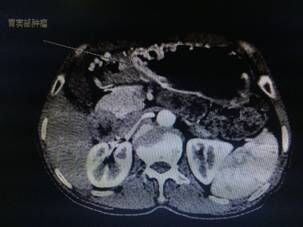

我院胃腸外科今年3月收治一名男性患者,以反復(fù)腹痛7月入院,CT提示胃竇部及乙狀結(jié)腸占位性病變(分別見圖1、2),行內(nèi)窺鏡活檢分別考慮胃腺癌以及乙狀結(jié)腸絨毛狀腺瘤,不排除惡變傾向。為改善患者生存率,減少創(chuàng)傷,手術(shù)團(tuán)隊決定充分發(fā)揮腹腔鏡技術(shù)優(yōu)勢,采用腹腔鏡下一期同時切除胃、結(jié)腸病變,由于患者乙狀結(jié)腸病變惡性診斷不明確,根據(jù)腫瘤根治的原則,先處理乙狀結(jié)腸。手術(shù)當(dāng)中依據(jù)冰凍切片,在腹腔鏡下首先完成乙狀結(jié)腸癌根治,后行腹腔鏡下遠(yuǎn)端胃癌根治術(shù)。一次微創(chuàng)手術(shù),切除兩個腫瘤,免除了患者傳統(tǒng)剖腹手術(shù)及二次手術(shù)的創(chuàng)傷,縮短了住院時間,術(shù)后恢復(fù)快,降低了患者住院費用。

圖片1                               圖片2